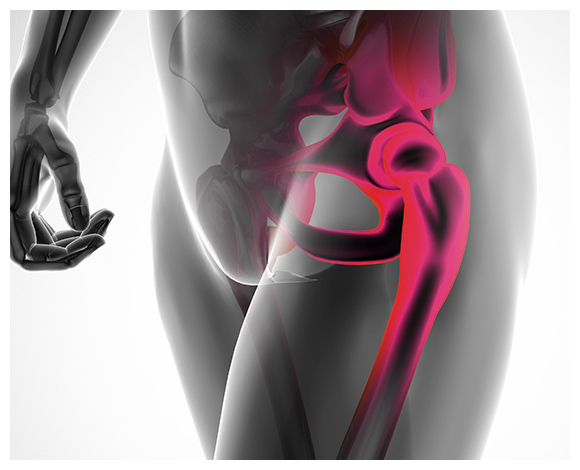

고관절이란?

고관절 통증 증상(엉덩관절)은 오른쪽과 왼쪽의 골반과 넙다리뼈가 연결된 관절의 통증을 일컫습니다. 고관절은 상체의 하중을 분산시키는 역할을 하며, 일어서거나 앉거나 일상생활에서 자주 쓰이는 관절이며 부담도 잘 받게 됩니다. 모양도 크기도 탁구공만 합니다. 일상적으로 걸을 때 고관절에 체중의 3~4.5배의 무게가 실리게 됩니다. 계단을 오를 때는 대퇴골두에 전해지는 무게는 몸무게의 8배, 달리는 경우 10배에 가까운 하중을 견뎌내애 한다고 합니다. 탁구공 크기만 한 대퇴골두가 감당하기에는 너무 무겁기 때문에 고관절이 느끼는 부담도 크고 쉽게 손상될 수 있습니다. 다른 관절과 마찬가지로 감당하기 어려운 충격이나 무게가 가해지면 고관절 통증 증상이 발생하게 되는데요. 퇴행성 고관절염, 대퇴골 골절, 대퇴골두 무혈성 괴사, 선천성 고관절 탈구 등이 대표적인 고관절 통증 질환입니다.